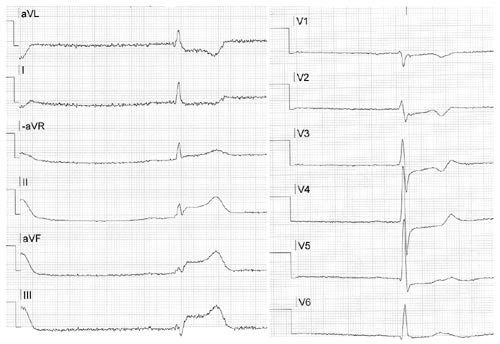

Ved Hjertemedisinsk avdeling, Ullevål universitetssykehus, ble det i april 2001 oversendt et prehospitalt EKG av en kvinne med brystsmerter. Det tydet på et akutt nedreveggsinfarkt (pasient 1 i tab 1, fig 1, fig 2). Hun fikk både acetylsalisylsyre og heparin etter gjeldende rutiner. Ved påfølgende angiografi fant man en A-disseksjon i torakalaorta. Vi ønsket derfor retrospektivt å vurdere pasienter innlagt med A-disseksjon for å se i hvilken grad de hadde EKG-forandringer ved innkomst og også i hvilken grad de primært var klassifisert og behandlet som ved akutt hjerteinfarkt.

Pasient 1. 73 år gammel kvinne med kjent hypertensjon, ellers frisk. Hun fikk akutt innsettende retrosternale brystsmerter med utstråling til halsen, og var sirkulatorisk ustabil med hypotensjon. Legebemannet ambulanse sendte prehospitalt EKG til hjerteovervåkingen 1/2 time etter debut av brystsmerter (fig 1). EKG ble tolket som forenlig med akutt nedreveggsinfarkt, pasienten fikk acetylsalisylsyre og heparin, og ble deretter kjørt til angiografilaboratoriet for primær angioplastikk. Ved kontrastinjeksjon i høyre koronararterie fant man imidlertid en A-disseksjon med aortainsuffisiens grad 3. I tillegg fant man en høygradig hovedstammestenose både på høyre og venstre side (fig 2). Pasienten ble derfor umiddelbart operert med bypass til høyre koronararterie, man valgte peroperativt ikke å legge bypass til venstre koronararterie. Postoperativt protrahert forløp, overflyttet lokalsykehus for mobilisering.